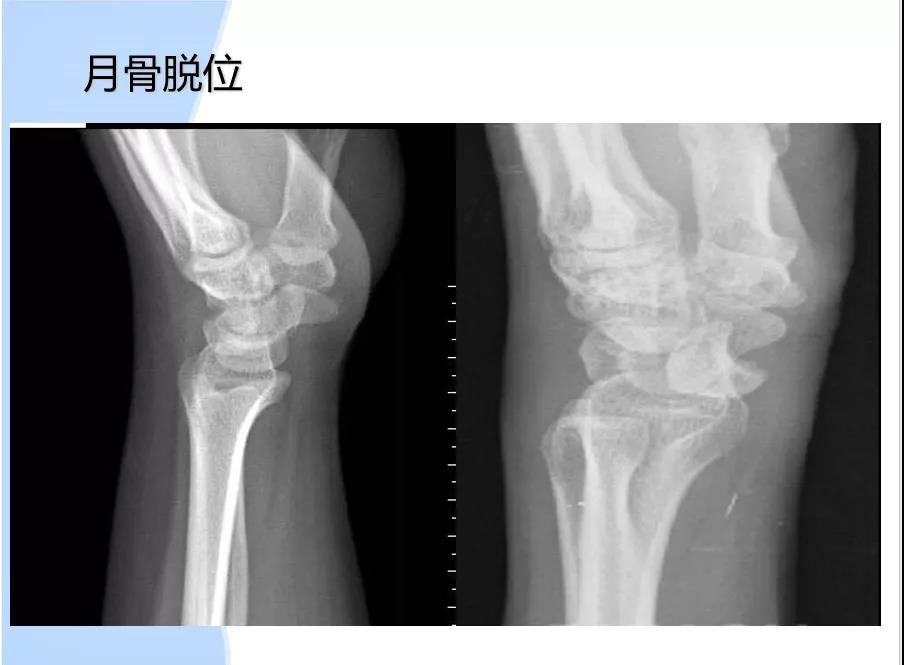

病因:1、腕管容量减小:月骨前脱位,腕部骨折(colles 反colles smith);腕和腕间关节增生性关节炎;腕横韧带增厚;感染或外伤致软组织水肿。2、腕管内容物增加:肿瘤(脂肪瘤、黄色瘤);腱鞘囊肿;腱鞘滑膜炎;3、解剖异常。4、正中动脉压迫。5、腕管内出血:外伤或血友病引发腕管内出血。6、其他:绝经;妊娠;痛风;类风湿;甲状腺功能低下。

诊断1 临床表现。2 Tinel征阳性。3 Phalen征阳性。4 X-ray鉴别骨折、脱位及增生。